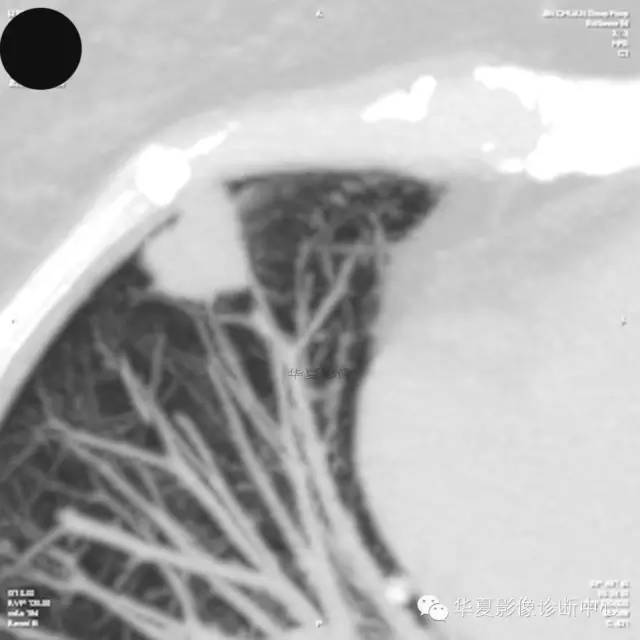

【病例学习】典型周围型肺癌CT病例一例

女,56岁,其父因肺癌去世,自觉胸部疼痛不适来诊要求拍胸片。

1.右肺上叶:肺组织1块,大小13×4×7cm。切面棕红色。2.右肺上叶肿物:灰白色组织一块,大小3×1×1.5cm。切面灰白色。3.右肺中叶结节:灰白色绿豆大组织1块。4.淋巴结:灰黑色绿豆大组织1块。

(右)肺中分化鳞状细胞癌。浸及胸膜。支气管残端切净。淋巴结未见癌转移(0/10)。